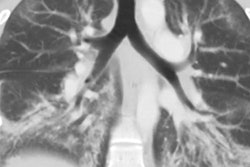

Presenter Ke Yan, PhD, from the U.S. National Institutes of Health (NIH) said he developed the multitask universal lesion analysis network (MULAN) to help radiologists save time and improve their accuracy. MULAN can help radiologists find, describe, and delineate a variety of lesions on CT, he said.

"This is the first algorithm that can do the three tasks jointly on many lesion types, thanks to the DeepLesion dataset our lab released last year," Yan told AuntMinnie.com. "It proves that computers have the capacity to remember the appearance of a lot of lesions, given sufficient training data."

After training, the algorithm yielded 84.8% detection sensitivity at a rate of one false positive per image, as well as an area under the curve of 0.96 for lesion tagging. The mean absolute error for the lesions' Response Evaluation Criteria in Solid Tumors (RECIST) diameters, calculated from the segmentation results, was 1.97 ± 2.24 mm.